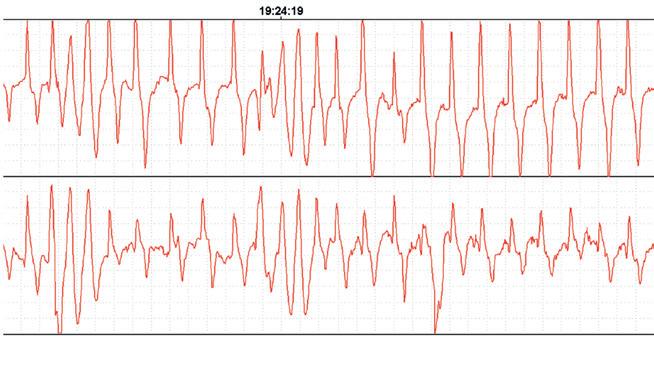

LEFT: An ECG from a racehorse shortly after crossing the finishing line. In this case the horse is exhibiting serious disturbances of heart rhythm. Interval between beats varies constantly and even when interval appears stable, the conformation of the waveforms is abnormal and variable. Waveform height also varies constantly. This horse returned to normal heart rhythm spontaneously as heart rate fell and continued to race successfully for the following year. There was no opportunity to test this horse for bleeding. However, no clinical signs were observed and had the horse not been undergoing research observation, the arrhythmia would not have been detected. The significance of these variations in the horse remains poorly understood. Similar variations under exercise conditions in humans would be regarded as pathological.

Image Dr. Peter Physick-Sheard, University of Guelph.

Although we talk about heart rate as a fairly stable event, there is in fact quite a lot of variation from beat to beat. This is often referred to as heart rate variability. There has been a lot of work performed on the magnitude of this variability at rest and in response to various short-term disturbances and at light exercise in the horse, but not a lot at maximal exercise. Sustained heart rate can be very high in a strenuously working horse, with beats seeming to follow each other in a very consistent manner, but there is in fact still variation.

Some of this variation is normal and reflects the influence of factors such as respiration. However, other variations in rate can reflect changes in heart rhythm. Still other variations may not seem to change rhythm at all but may instead reflect the way electrical signals are being conducted through the heart.

These may be evident from the ECG but would not appear abnormal on a heart rate monitor or when listening. These variations, whether physiologic (normal) or a reflection of abnormal function, will have a presently, poorly understood influence on blood flow through the lungs and heart—and on cardiac filling. Influences may be minimal at low rates, but what happens at a heart rate over 200 and in an animal working at the limits of its capacity?

Normal electrical activation of the heart follows a pattern that results in an orderly sequence of heart muscle contraction, and that provides optimal emptying of the ventricles. Chamber relaxation complements this process.

An abnormal beat or abnormal interval can compromise filling and/or emptying of the left ventricle, leaving more blood to be discharged in the next cycle and back up through the lungs, raising pulmonary venous pressure. A sequence of abnormal beats can lead to a progressive backup of blood, and there may not be the capacity to hold it—even for one quarter of a second, a whole cardiac cycle at 240 beats per minute.

For a horse that has a history of bleeding and happens to be already functioning at a very marginal level, even minor disturbances in heart rhythm might therefore have an impact.